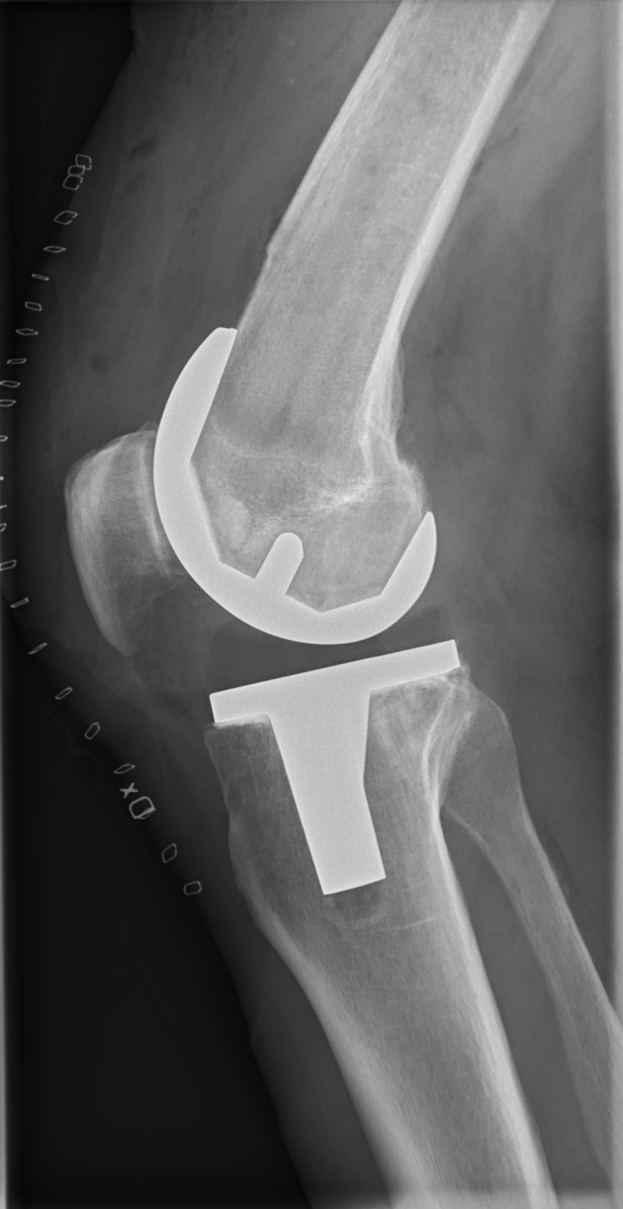

Ein Röntgenbild eines menschlichen Beins mit einem sichtbaren Bruch im Kniebereich, wahrscheinlich eine Bänderverletzung.Walburga Hornig